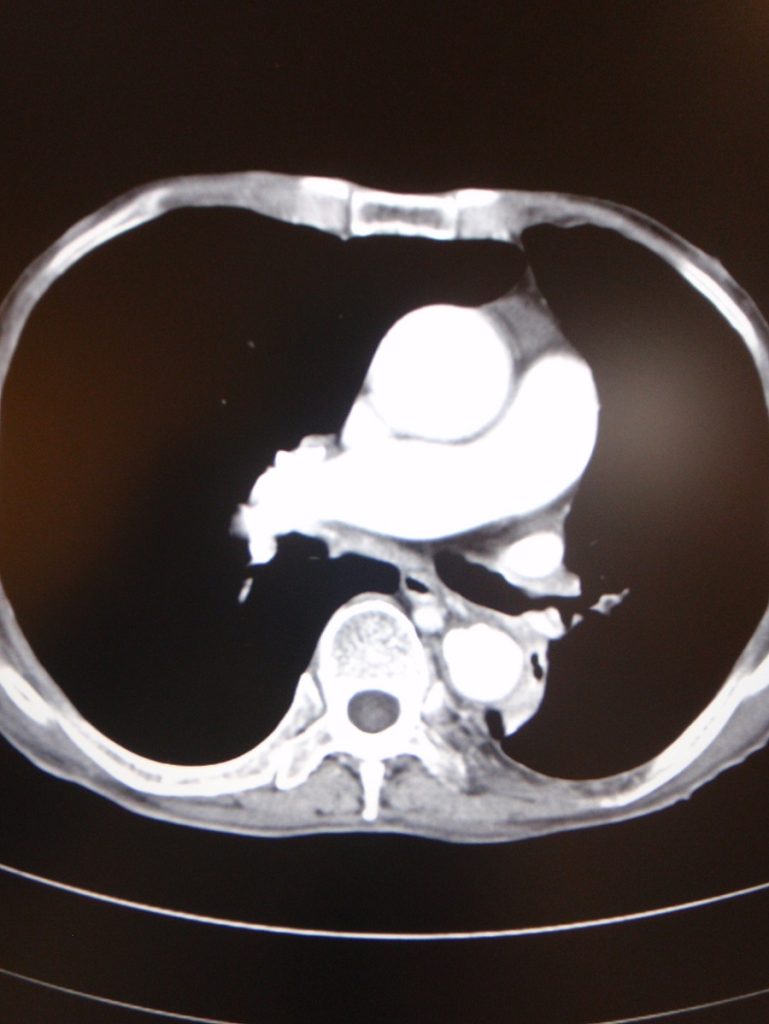

Computerized tomogram of thorax on 6 April 2010 for KH showed an enhancing lesion at left infrahilar region measuring 1.5 x 2.3 x 2.5cm in LLL with erosion into LLL bronchus. (fig. 2)

Fig.2 (Above) Patient 1: Computerized tomogram of thorax on 6 April 2010 showed an enhancing lesion at left infrahilar region measuring 1.5 x 2.3 x 2.5 cm in LLL with erosion into LLL bronchus.